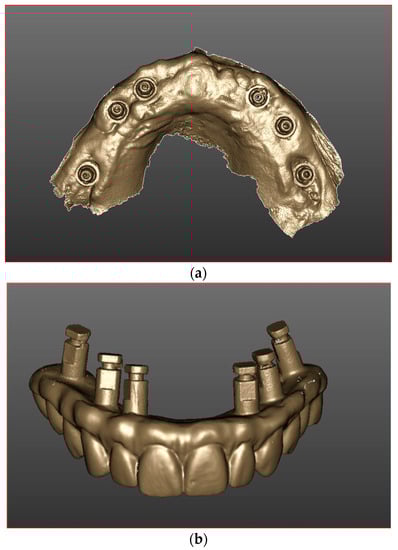

2.5. Prosthetic Protocol